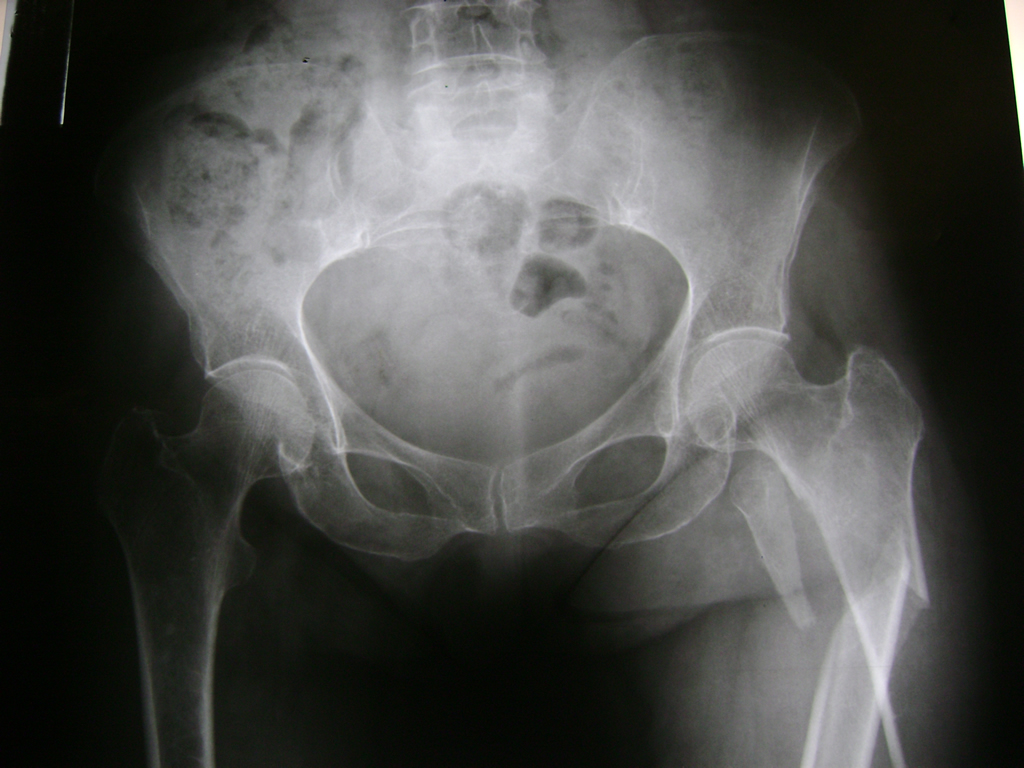

Fémur - Cadera

La cirugía de fractura de cadera se realiza para reparar una ruptura en la parte superior del hueso del muslo. Este hueso se denomina fémur.

Es parte de la articulación coxofemoral. Si una fractura de cadera no recibe tratamiento, es posible que deba permanecer en una silla o en la cama.